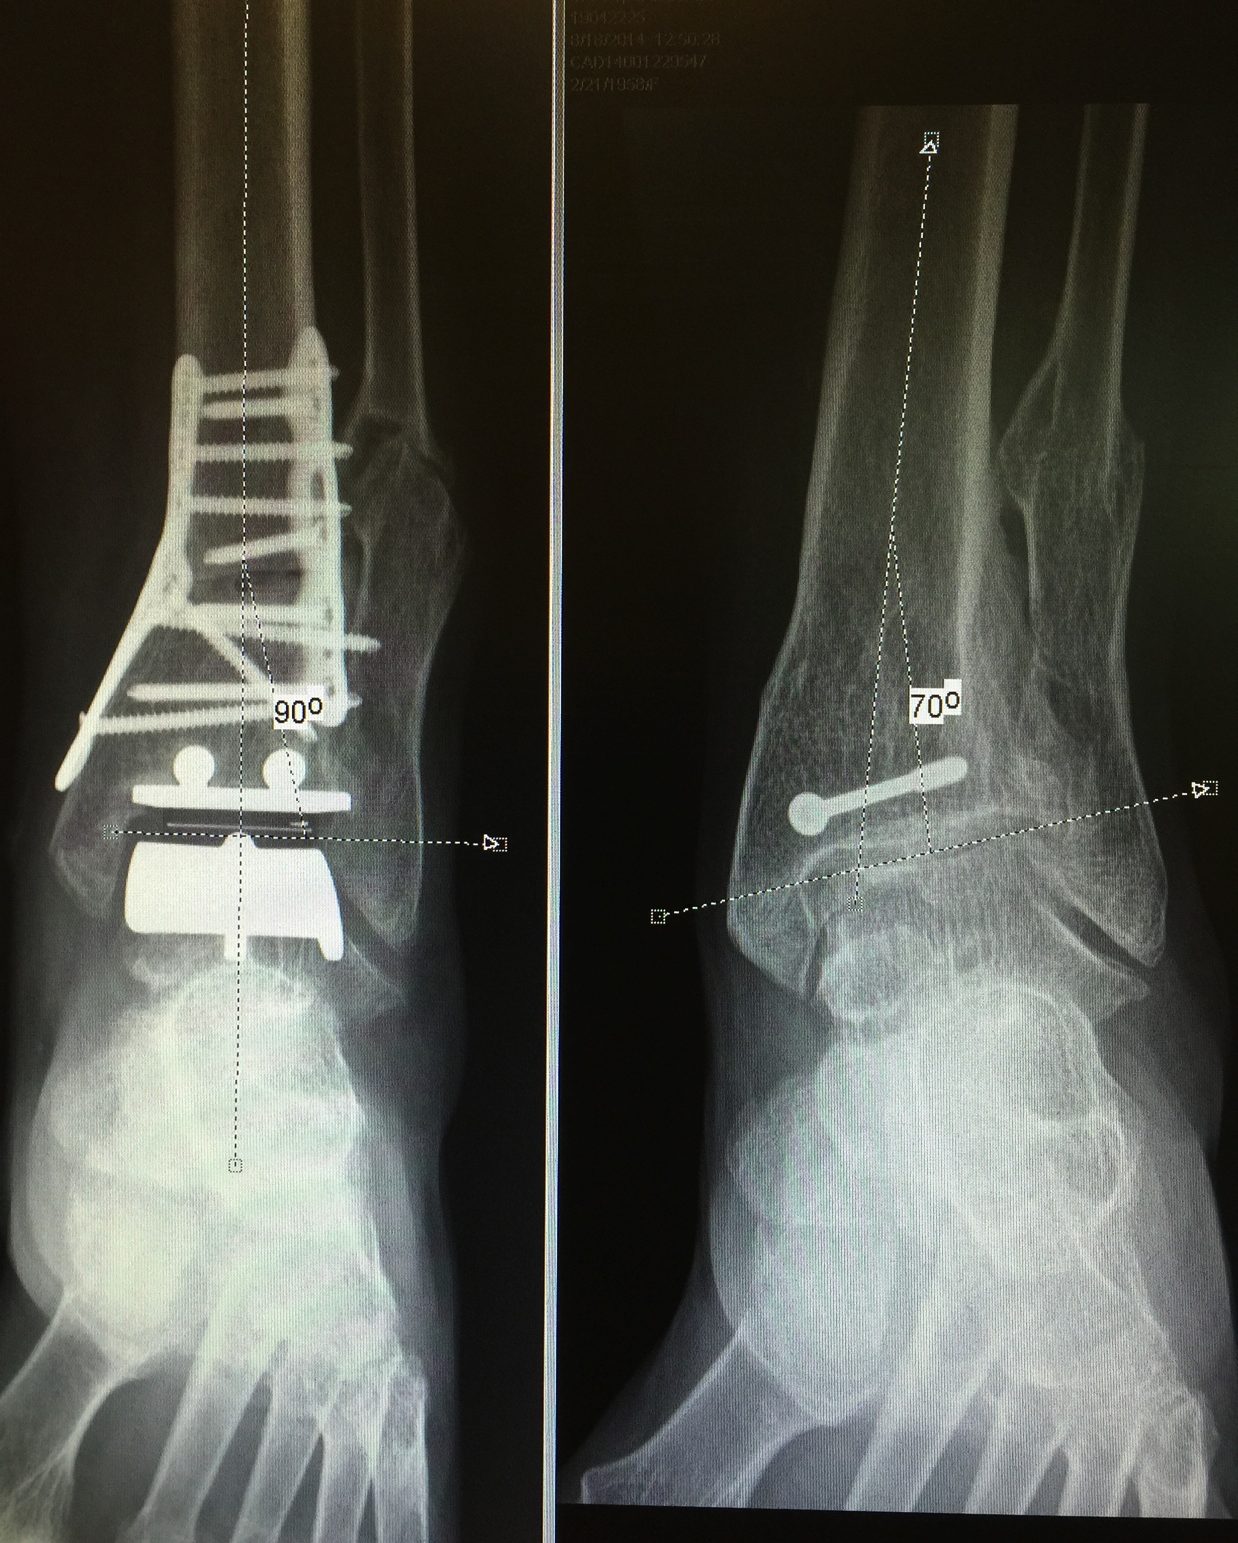

The ankle joint (tibiotalar joint) is where your shin bone (tibia) rests on top of a bone of your foot (talus). Common procedures in ankle surgery can include ankle arthroscopy, ankle replacement, ankle fracture repair surgery, ankle fusion, and lateral ankle ligament reconstruction. It is a treatment option for people with advanced ankle osteoarthritis. Ankle replacement surgery is the replacement of the damaged cartilage and bone in the ankle joint with an artificial implant. However, not everyone is an eligible. Recovery will take several weeks. Hss has a dedicated team of doctors, nurses and physical therapists with extensive replacement experience. Ankle replacement surgery involves replacing the ankle joint with a prosthesis. Ankle arthroscopy is very common, and surgeons are able to treat more conditions than ever before thanks to recent technological advances. Ankle replacement is a common surgery that might be recommended if damage to your ankle joint makes it hard for you to walk or do daily tasks.